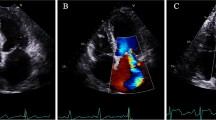

Illustration of quantitative assessment of left ventricular (LV) volumes in a patient with isolated functional mitral regurgitation (FMR)—part 1: a scheme of LV effective stroke volume (LVSVeff) and regurgitant volume (RegVolMV) in isolated FMR (a); measurements of right ventricular (RV) and LV stroke volume by Doppler echocardiography (RVSVDopp, LVSVDopp) by determination of the diameter of the RV outflow tract (RVOT) (b) and the velocity time integral (VTI) of the RVOT (RVOT VTI) (c) and by determination of the diameter of the LV outflow tract (LVOT) (d) and the LVOT VTI (). In isolated FMR RVSVDopp is equal to RVLVDopp, which represents LVSVeff as well as RVSVeff. LVSVeff is between 65 and 70 ml in this case

Illustration of quantitative assessment of left ventricular (LV) volumes in the same patient with isolated functional mitral regurgitation (FMR) as shown in Fig. 1—part 2: determination of left ventricular (LV) total stroke volume (LVSVtot) by biplane planimetry using Simpson’s method; planimetry of the 2-chamber view during diastole (a, b) and systole (c, d), planimetry of the 4-chamber view during diastole (e, f) and systole (g, h); the biplane LV planimetry enables the determination of LVSVtot, which is the sum of LV effective stroke volume (LVSVeff) and of the regurgitant volume (RegVolMV); LVSVtot is between 85 and 90 ml in this case

Illustration of quantitative assessment of left ventricular (LV) volumes in the same patient with isolated functional mitral regurgitation (FMR) as shown in Figs. 1 and 2—part 3: documentation of the FMR with a central jet formation, the jet area, the proximal convergence areas, and the vena contracta (VC) with a Nyquist limit of 47 cm/s (a), VC measurement with 4 mm (b), the basal septal myocardial velocity for calculation of E/E′ (c), the pulsed wave Doppler spectrum for determination of E velocity, the E/A-ratio and the ratio between transmitral velocity time integral (VTI) and flow velocity within the LVOT (VTIMV/VTILVOT) (d), and the continuous wave Doppler spectrum of the transtricuspid regurgitation for estimation of the systolic pulmonary arterial pressure (sPAP) (e); increased E/E′, increased E-velocity, increased VTIMV/VTILVOT and increased sPAP document the secondary cardiac alterations of a relevant MR

Illustration of quantitative assessment of left ventricular (LV) volumes in the same patient with isolated functional mitral regurgitation (FMR) as shown in Figs. 1, 2 and 3—part 3: determination of regurgitant volume (RegVolMV) by the 2D-PISA method—the jet phenomenon at systole using a Nyquist limit 47 cm/s (a), measurement of the mean and maximum regurgitant velocities (b), labeling of the 2D-PISA radius at a Nyquist limit of 19 cm/s (c), the estimation of RegVolMV in this case, in which the 2D-PISA method is allowed to be used, results in a value of about 15–20 ml; the volumes LVSVtot, LVSVeff, RVSVeff, and RegVolMV have to be conclusive and plausible; exclusion of additional relevant valvular diseases (d–f); color-coded image of the left ventricular outflow tract during diastolic documents the exclusion of aortic regurgitation (AR) (d), the respective continuous wave Doppler spectrum documents no regurgitant signal (e), and a trace tricuspid regurgitation during systole is documented (f)

The quantitative approach of FMR assessment by echocardiography is challenging. The quantitative assessment of LV volumes is highly criticized because of the necessity to determine several parameters, which are all prone to measuring errors that are squared in the respective calculations [8, 9]. Nevertheless, in isolated FMR, the LVSVtot is determined by LV planimetry using the monoplane, biplane, triplane or 3D approach. The LVSVeff is measured by Doppler calculations of forward stroke volume using cross sectional area of the LVOT and the PW-Doppler velocity time integral (VTI) of the LVOT. In patients with combined aortic valve disease the LVSVeff can be determined by Doppler calculations of SV using cross sectional area the right ventricular outflow tract (RVOT) and the respective PW-Doppler VTI of the RVOT which is not common use in clinical routine echocardiography. As illustrated LV volumes and RegVolMV can be correctly calculated by the differences of LVSVtot and LVSVeff or RVSVeff, and in few cases, in which the 2D-PISA method can adequately be used, the calculated RegVolMV corresponds to the RegVolMV determined by the 2D-PISA method (Figs. 6, 7, 8, 9). If all parameters can be assessed, a cross-check can be well performed with respect to plausible hemodynamics [37]. To provide a precise echocardiographic characterization of FMR severity the presented quantitative TTE approach might be additionally added to the “up to now integrated approach” to provide a more reliable and more consistent characterization of the FMR severity.